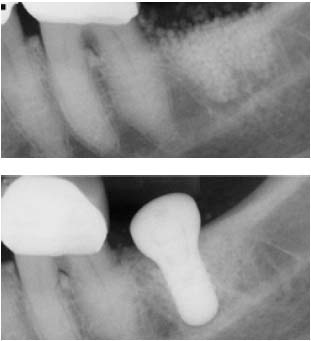

セラソルブは、X線造影性に富んでいます。下記写真をご覧ください。

![]() 骨補てん材

骨補てん材